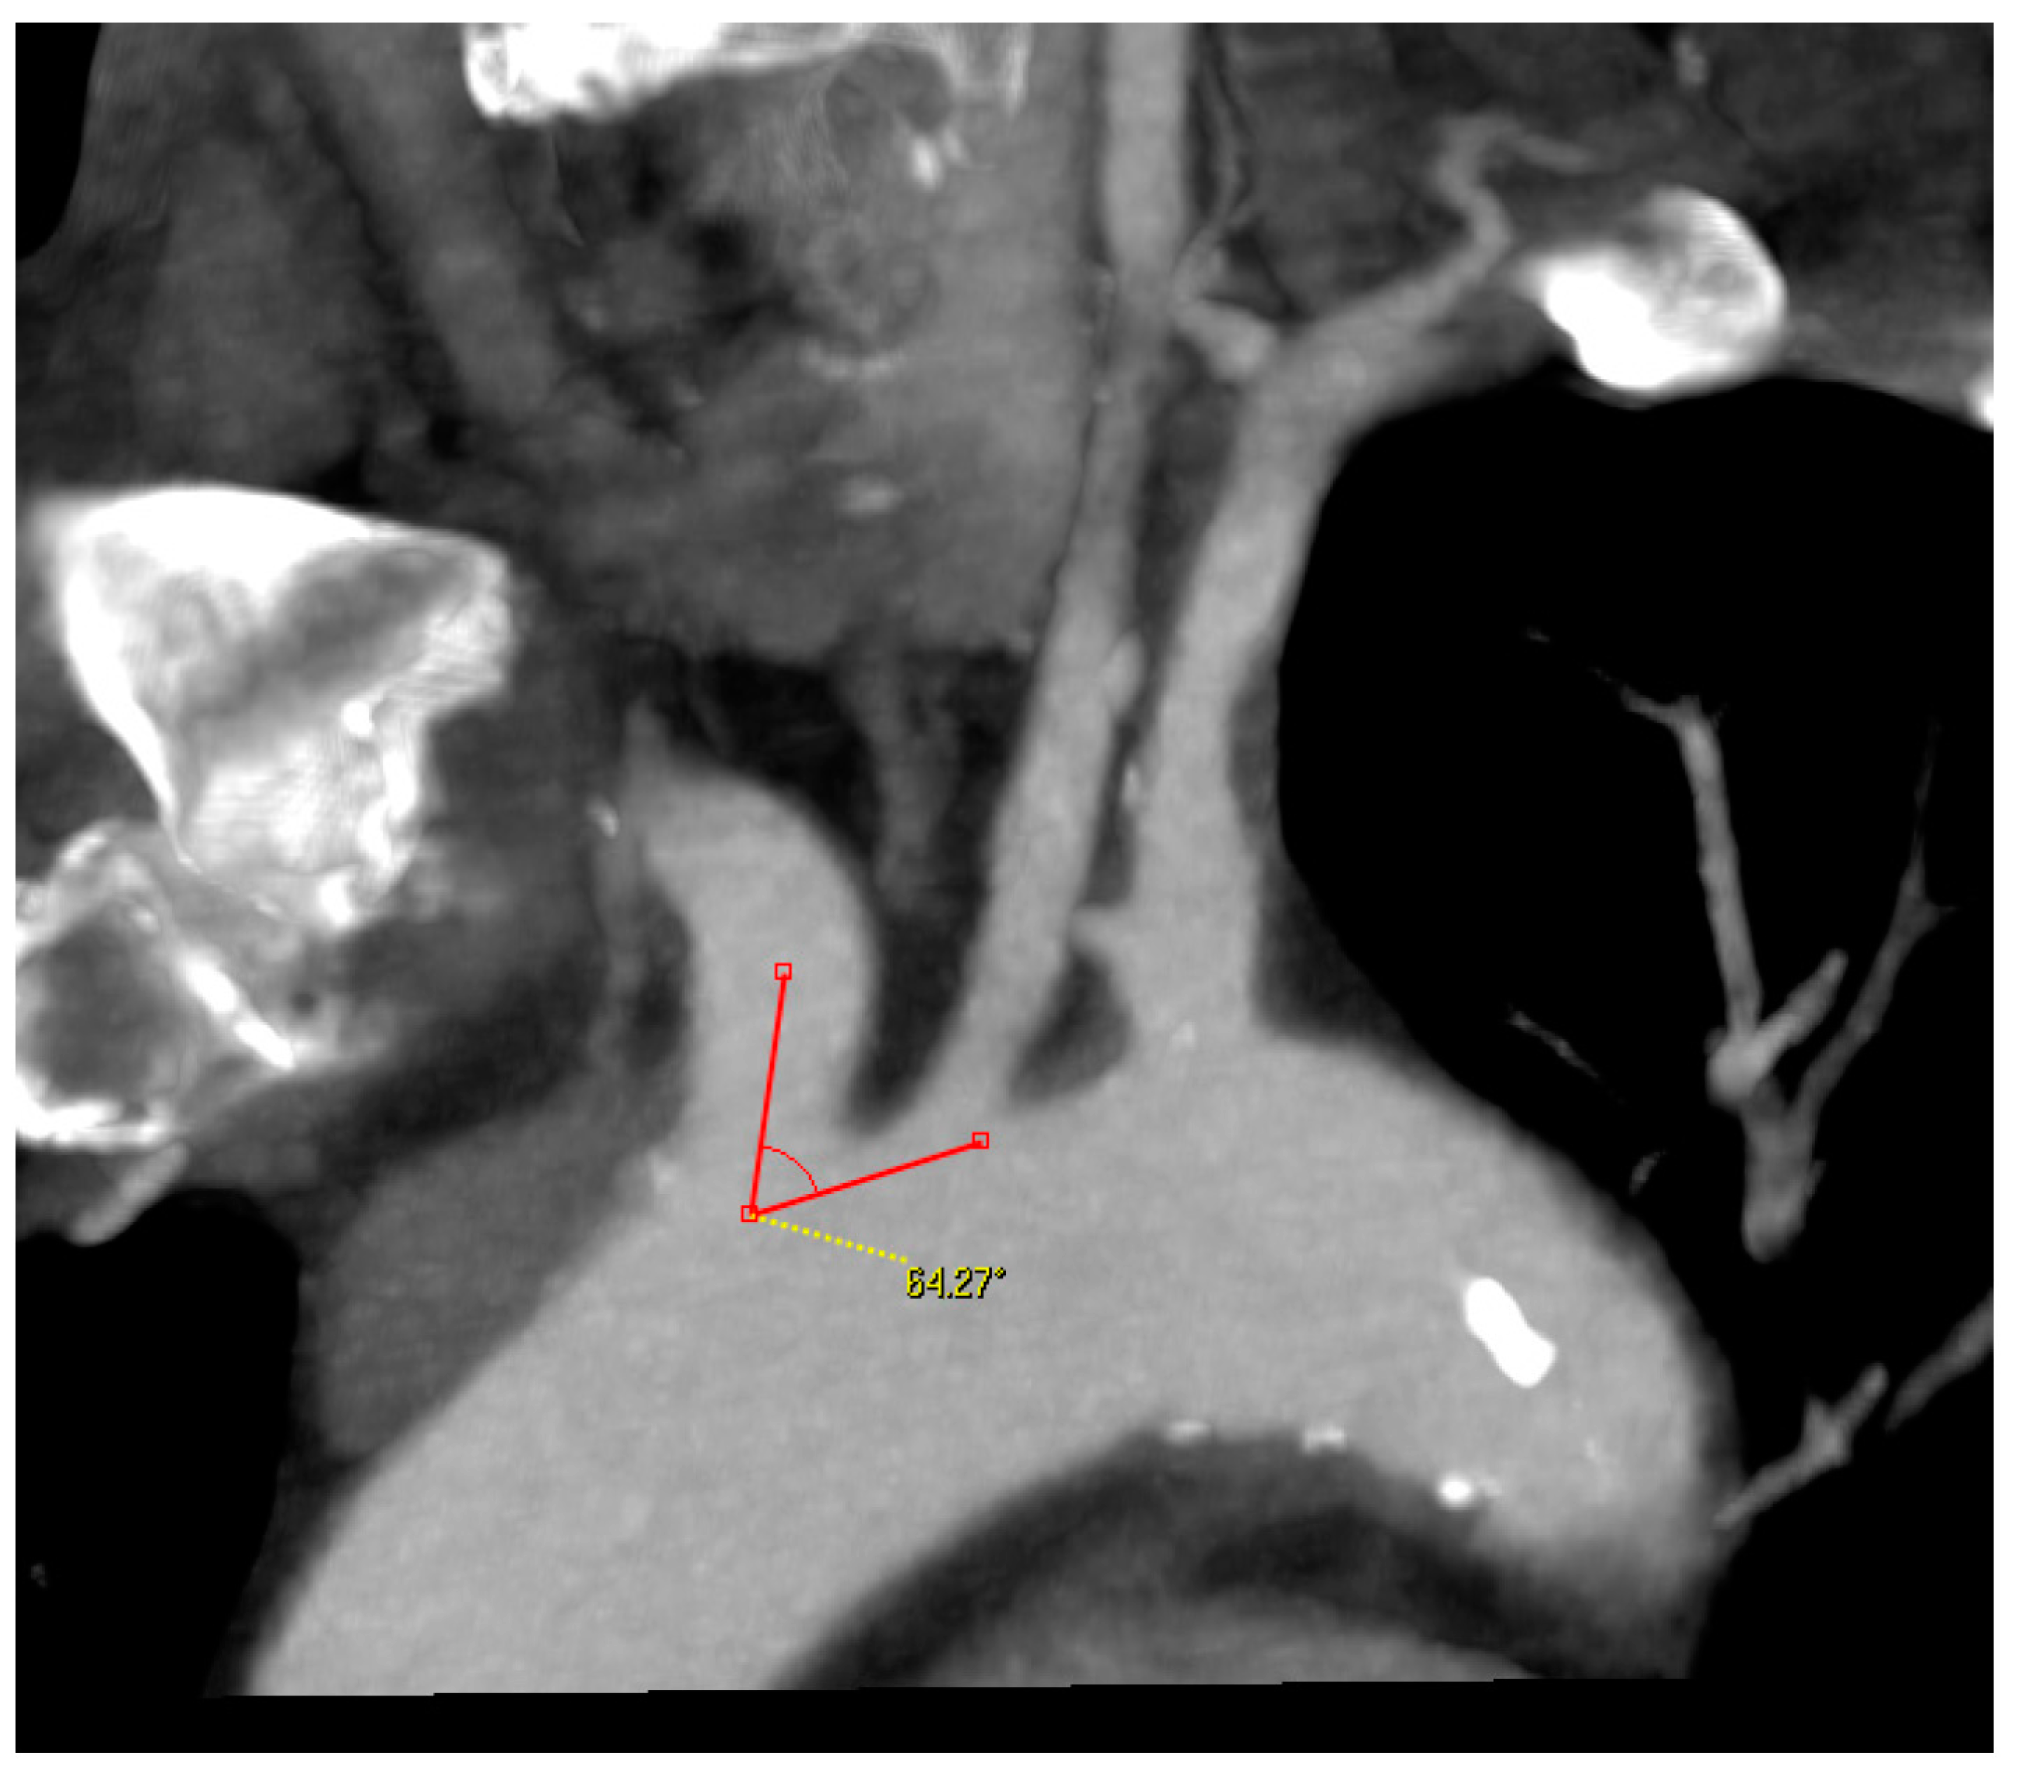

- Angle between the AA and the supra-aortic vessel: measured on the treated side only, through a multiplanar reconstruction and visualization of the AA in coronary and left anterior oblique (LAO) projection. One arm of the angle was drawn along the outer curvature of the AA and the second arm was placed in the middle of the CCA or brachiocephalic trunk. The right-side angle was chosen for selection criteria (Figure 3);

Figure 3. Angle measurement between the aortic arch and supra-aortic vessel.

The perioperative incidence of stroke and death was lower in this study than in the RCTs that compared CAS against CEA for both symptomatic and asymptomatic patients. Based on our results, anatomical criteria should be taken into account when determining the indication for CAS. For cannulating the CCA, the angle between the AA and the supra-aortic vessel, as well as the AA-type, play very important roles. The AA changes over time, and these changes are caused, among other things, by atherosclerosis, arterial hypertension, and age. AA remodeling results in elongation of the AA and caudal positioning of the supra-aortic vessels [20]. At the same time, the difficulty of cannulating the supra-aortic vessels increases parallel to the AA-type, and simultaneously with an increased risk of embolization due to the required manipulations in the AA [21,22]. In our institution, a type III AA is considered a contraindication for transfemoral cannulation of the carotid artery.

The remodeling changes in the AA cause a variation in the angle between the AA and supraaortic vessels. Based on the available literature on this topic, it is still currently not possible to recommend an exact angle for CAS. Suh et al. reported that the angle between the AA and CCA is significantly smaller on the left side than with the brachiocephalic trunk. The left CCA originates from the AA and has an oblique course from right to left and from caudal to cranial. On the other hand, the CCA to the right side has a much straighter course [23]. We have generally treated moderate-grade angles, with no obtuse or acute angles. It was particularly interesting in this study that the angle on the left side was 10° smaller than on the right side. This confirms the assumption of Suh, G.Y. and is a possible explanation for why left-sided supra-aortic interventions are technically more difficult and are associated with higher complication rates [24,25]. Our results also showed that the angle of the type I AAs were greater than the type II AAs.